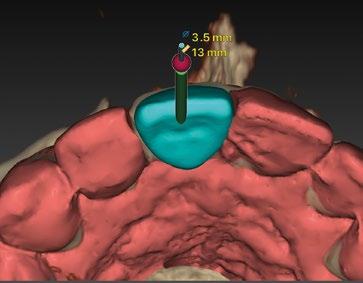

Con todos estos datos fusionados en el DTX StudioTM Implant, lo que vamos a hacer es utilizar la función SMARTSETUP para tener un encerado Virtual que nos permita determinar la posición de la futura restauración del paciente, en función de la cual colocaremos nuestro implante y el aditamento más adecuado. (Figura 8)

En este caso, podemos ver que tenemos un defecto óseo vestibular, se trata de un defecto de una sola pared de la zona a implantar.

Intentamos planificar un implante inmediato y observamos la posibilidad de tener un buen anclaje apical por lo tanto nuestra primera opción va a ser la realización de un implante post extracción con regeneración de la pared vestibular mediate xenoinjerto óseo e injerto de tejido conectivo para mejorar el biotipo. (Figura 9)

En el caso de obtener suficiente torque, podríamos incluso valorar la opción de cargar dicho implante. En este caso lo que hacemos es planificar también un pilar con el fin de trabajar nuestra prótesis a nivel gingival, siguiendo la filosofía de “One Abutment-One Time (OAOT)”.

Lo realmente extraordinario de este software de diagnóstico y planificación es que en una sola imagen tenemos total control de la posición de nuestro implante y de nuestro pilar, en función del hueso de la encía y de la futura restauración. Por lo tanto vamos a realizar una implantología protética, y biológicamente guiada. (Figura 10)

Planificación

Una vez tenemos todos los datos, decidimos como primera opción realizar una cirugía guiada post extracción con regeneración y carga inmediata.

10.- Colocamos implante Nobel Biocare N1TM TiUltra de 3,5x13. (Figura 26)